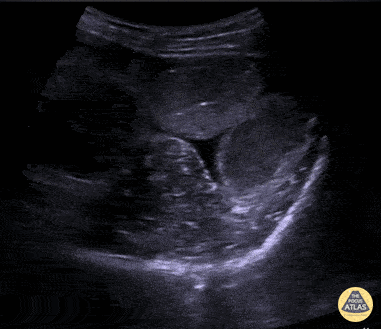

Bowel-GI - SBO Demonstrating To-and-Fro Peristalsis

Middle age male patient with past history of multiple abdominal surgeries, presented with clinical picture of intestinal obstruction. POCUS was performed demonstrating dilated bowel loops up to 3.3 cm with clear "to-and-fro" movements of bowel contents on the right side of the screen. Learning point: Keep the ultrasound probe still and wait for enough time to allow the back and forth "to-and-fro" movements of the bowel content. Contributor: Basel Elmegabar; MBBS